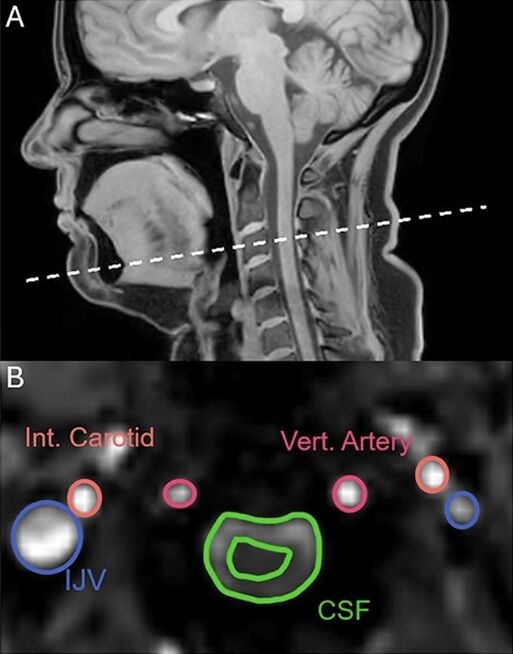

Автори роботи – команда з Університету Нового Південного Уельсу в Австралії – досліджували фізіологію позіхання за допомогою магнітно-резонансної томографії. У дослідженні взяли участь 22 здорові добровольці. Їм по черзі пропонували позіхати, глибоко вдихати, стримувати позіхання та дихати у звичному режимі. Наразі робота ще не пройшла рецензування, але вже опублікована на платформі bioRxiv.

Оскільки позіхання та глибокий вдих мають схожі механізми, дослідники припускали, що й результати МРТ будуть майже ідентичними. Проте скани показали принципову різницю. На відміну від глибокого дихання, позіхання змушувало спинномозкову рідину рухатися від мозку, а не до нього. Це стало ключовим і несподіваним відкриттям.

Як пояснив виданню ScienceAlert нейробіолог Адам Мартінак, позіхання викликало протилежний рух рідини порівняно з глибоким вдихом: “Позіхання запускало рух спинномозкової рідини у протилежному напрямку, ніж під час глибокого вдиху”, – зазначив він. Науковець зізнався, що команда не очікувала такого результату: “І ми просто сидимо там і думаємо: ого, ми точно такого не очікували”.

Окрім руху спинномозкової рідини, аналіз показав ще одну важливу деталь. І глибоке дихання, і позіхання посилюють відтік крові від мозку. Це, своєю чергою, створює простір для надходження нової, насиченої киснем крові. На ранніх етапах позіхання кровотік у сонній артерії збільшується приблизно на третину.